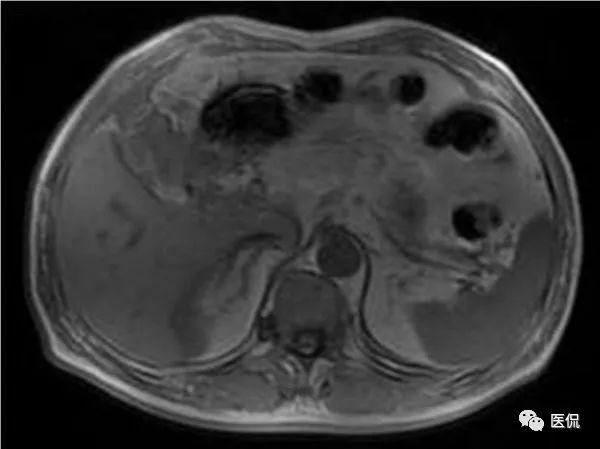

突发右中腹部隐痛,原因、诊断及治疗方法全解析

突发右中腹部隐痛是一种常见的健康问题,许多人在生活中都可能遭遇,这种疼痛可能由多种原因引起,需要及时关注并采取相应措施,本文将详细介绍突发右中腹部隐痛的原因、诊断方法及治疗方法,帮助大家更好地了解这一健康问题。症状及...